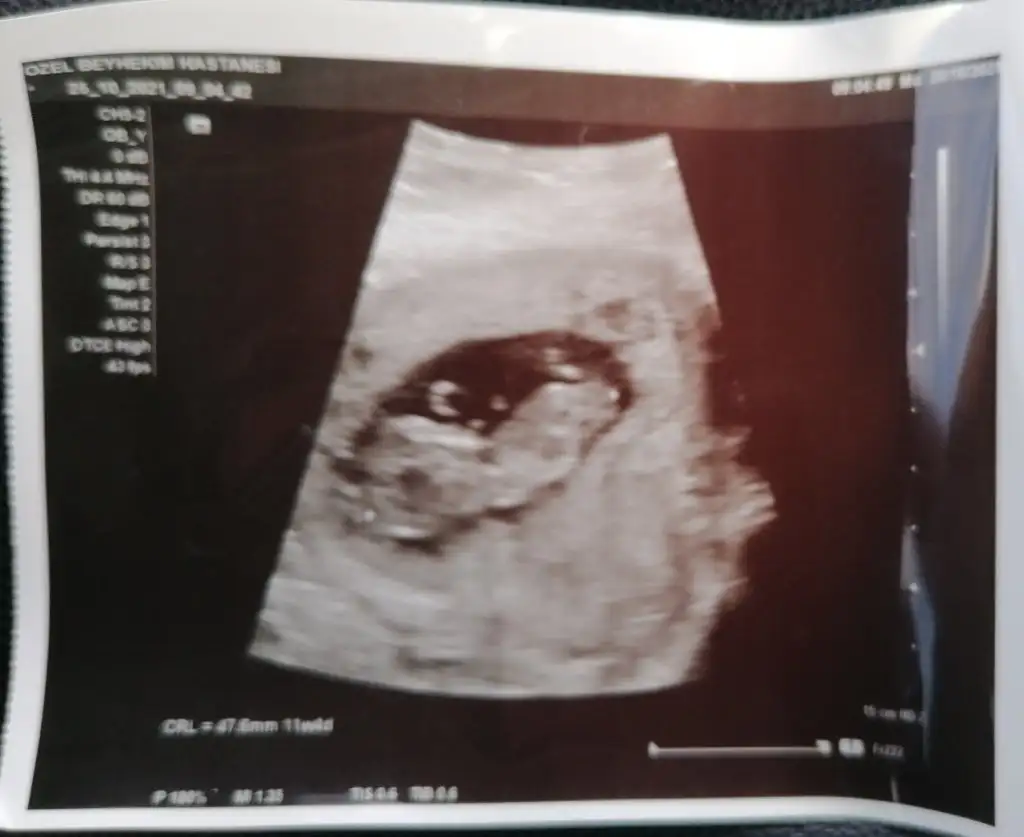

Ben de sizler gibiyim 13.haftanin icindeyim çift tarafli takip ettiriyorum kendimiZaten hiiç belli olmaz bizimde ne olucağı o yüzden iki yere de yazın benceöğrenenlerden hepimizin erkek diyim

ikili testler vs o durumlardayız sizin durumunuz nedirrr